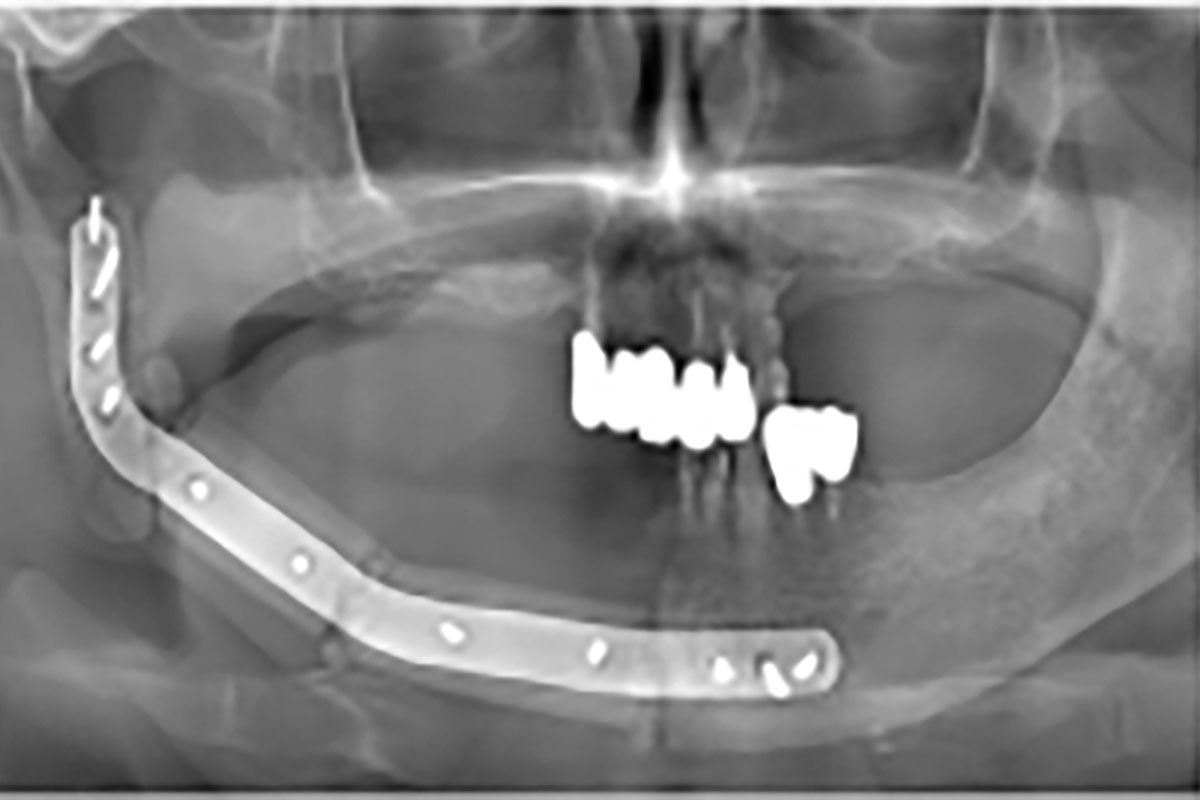

画像検査(パノラマX線、CT、MRI、骨シンチグラフィーなどの核医学検査)、血液検査、病理組織検査などを行います。

主に保存的な治療(洗浄、抗菌薬の投与)、外科的な治療(壊死している骨を除去する手術、顎の骨を切りとる手術、など)に分けられます。補助的な治療(高気圧酸素療法)を追加する事もあります。顎の骨を切る手術を行う場合は、金属のプレートや皮弁(自分の脚の骨など)による再建を行い、口を開ける、義歯を入れてご飯を食べる、などの口腔の機能を維持するようにしています。